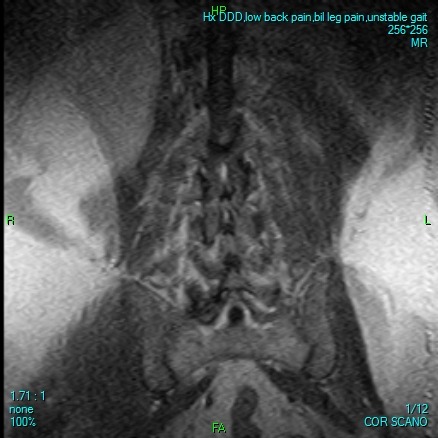

Some days he can barely stand or walk a few steps without collapsing in agony. Many nights, he lies alone, tears streaming down his face, praying for relief. His doctors have been clear: without urgent spinal surgery, he faces the devastating reality of becoming completely bedridden—possibly forever.

Desperate for relief, he trusted a foreign clinic that promised affordable treatment. Instead, they took advantage of him, leaving him stranded far from home in Mexico with no money to return. After months of struggle, honest and ethical doctors here in North America confirm they are prepared and able to perform the surgery he urgently needs. But the hospital requires $17,600 upfront to cover his Medicare deductible and uncovered costs before they can even admit him.